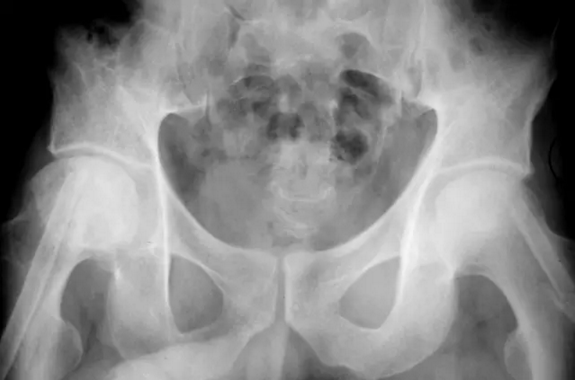

股骨头缺血坏死

在股骨头缺血性坏死患者的骨盆正位平片可见不对称关节间隙狭窄(箭头),近关节硬化,软骨下囊肿形成围绕右髋继发退行性骨关节病。